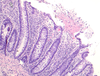

What is seen here?

Fungal esophagitis- Candida

- Pseudohyphae in squamous cells

- Yeast forms

Recall: Candida is part of flora in oral cavity; if just sitting in lumen, it’s probably contaminant. Must diagnose by seeing within tissue